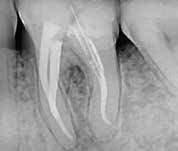

L’obiettivo finale della terapia endodontica è rappresentato dalla completa sigillatura degli spazi canalari, con la massima estensione sia in senso apicale che laterale.

Consiste nel creare un sigillo ermetico tridimensionale, stabile nel tempo, in grado di isolare e neutralizzare i microorganismi sopravvissuti alle precedenti procedure di sagomatura e detersione, “murandoli” sulle pareti canalari e all’interno dei tubuli dentinali.

Le basi biologiche dell’otturazione canalare

I primi concetti di allargamento, pulizia e otturazione e conseguente eliminazione dell’infezione peri-apicale risalgono all’ottocento.

I primi studi, all’inizio del secolo successivo riportavano affermazioni quali “i denti necrotici sono aperture attraverso la naturale barriera protettiva e agiscono come porta d’ingresso dell’infezione nell’organismo a meno che non vengano ermeticamente sigillati”...“le otturazioni canalari devono adattarsi così intimamente da impedire a fluidi e microorganismi di penetrarvi e trovarvi spazio”.